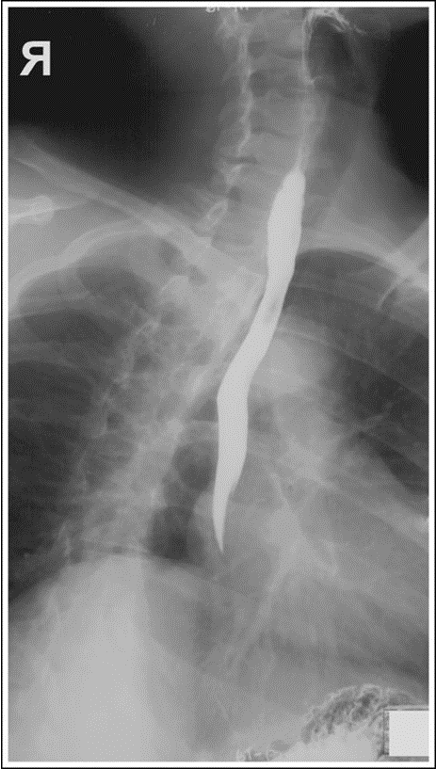

AP/PA Oblique (RAO or LPO) Esophagus (CR and Positioning)

Oblique patient 35 to 40 degrees. This obtains a wider space and unobstructed view of the esophagus between the vertebrae and the heart

RAO - Side down arm at the side and side up arm by the head

Shield patient

Place IR at the top of the mouth

CR - at the level of T5-T6 and 2 inches from the spine to the elevated side

Instruct patient ot take big swallows and expose while esophagus is full of barium

AP or PA Oblique Esophagram Eval Criteria

Esophagus between the vertebrae and the heart

RAO Esophagus with proper positioning

RAO Esophagus with superior and inferior no barium

RAO Esophagus with rotation less than 35-40 degrees